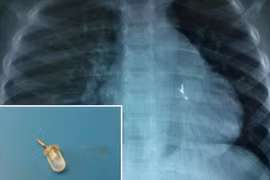

Báo động tình trạng hóc dị vật ở trẻ em

ANTĐ - Trong vòng nửa tháng trở lại đây, tại Hà Nội và TP.HCM đã tiếp nhận và cấp cứu nhiều trường hợp hóc dị vật ở trẻ nhỏ. Đáng báo động, những trường hợp này đều là các bé nhỏ, hóc phải những dị vật nguy hiểm, ảnh hưởng đến tính mạng.